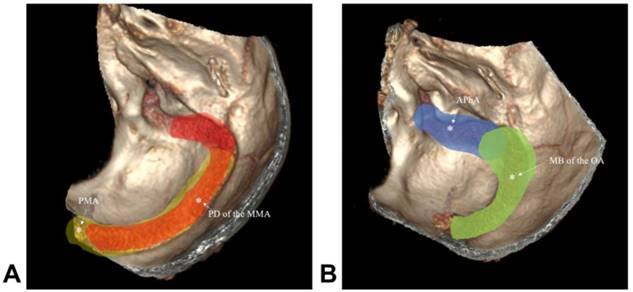

A 48-year-old man who presented with subarachnoid hemorrhage was admitted to our hospital. The DSA showed a TSS DAVF, and the feeding arteries included the petrous branch of the MMA and PMA. The venous drainage presented with cortical venous reflux. The TSS DAVF was embolized by PD of the MMA via a double-lumen balloon, which is known as the pressure cooker technique. After TAE, the TSS DAVF was cured. The typical case is shown in Figure 2.

Figure 2

Images of a typical case. A: CTA shows the dilated veins on the left TS, suggestive of DAVF; B: DSA of the left ECA shows the TS DAVF; PD of the MMA was the main feeding artery, and cortical venous reflux was observed; C: DSA of the vertebral artery showed that the PMA was also a feeding artery; D: the TS DAVF was embolized by PD of the MMA via a double-lumen balloon, which is known as the pressure cooker technique; E-F: DSA of ECA and vertebral artery show that the TS DAVF was cured. Abbreviations CTA: computed tomographic angiography; TS: transverse sinus; DAVF: dural arteriovenous fistula; DSA: digital subtraction angiography; ECA: external carotid artery; PD of the MMA: posterior division of middle meningeal artery; PMA: posterior meningeal artery.